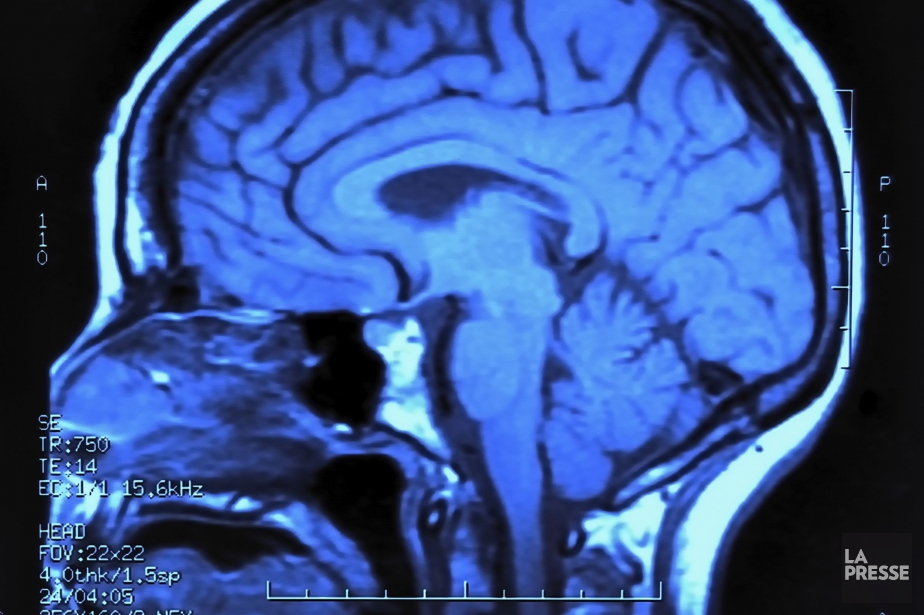

Ces recherches "laissent entrevoir la possibilité de guérir certains troubles de la vison grâce à des traitements neurologiques" en agissant directement sur "le cerveau et sa capacité à recevoir avec précision les projections de la rétine", explique la fondation dans un communiqué.

"C'est une véritable révolution", souligne le communiqué, soulignant que "la vision est fortement dépendante de ces connexions synaptiques entre la rétine et les centres visuels supérieurs du cerveau".